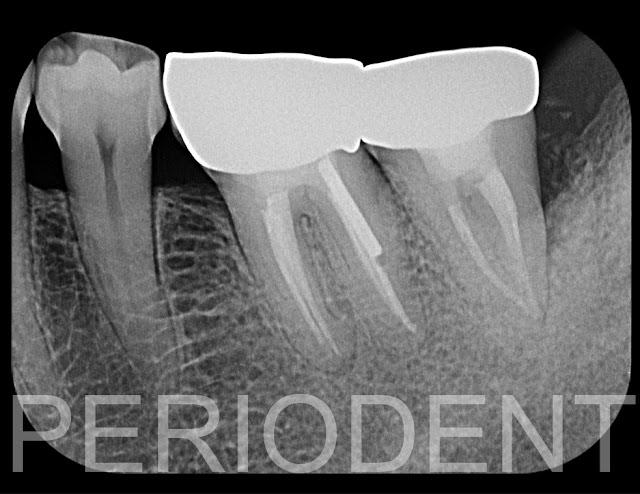

將左下第一大臼齒拆除,進行左下的牙齒的Splint,電腦斷層檢查,發現嚴重骨破壞,進行根管治療

再三個月後檢查時,電腦斷層檢查可見骨再生